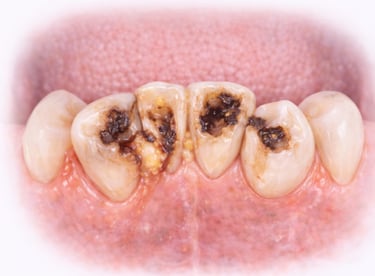

All images shown here represent real clinical cases of teeth extractions done at our dental clinic with patient consent.

Illustrative images and similar real clinical cases requiring tooth extraction